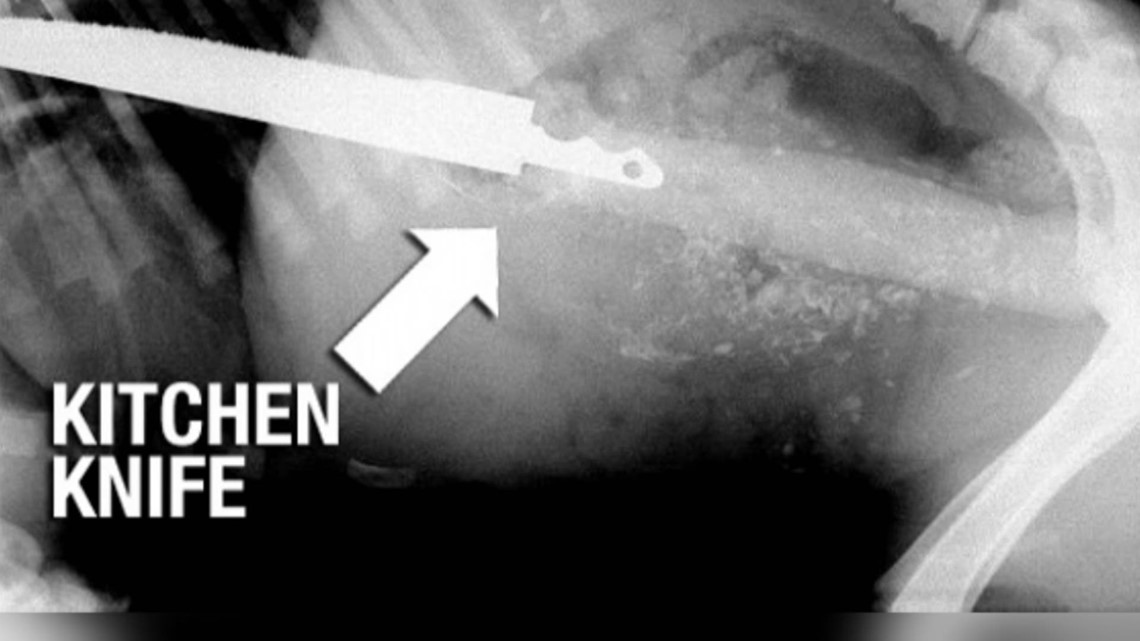

What should you do if your dog swallows something harmful? What If Your Dog Swallows Something signs that your dog may have swallowed something include vomiting, straining to defecate, diarrhea, lethargy, loss of. Most pets that have ingested a foreign body will exhibit some of these clinical signs: if your dog has swallowed something sharp, such as a bone fragment or needle, do not attempt to induce vomiting. how do i know if. What If Your Dog Swallows Something.